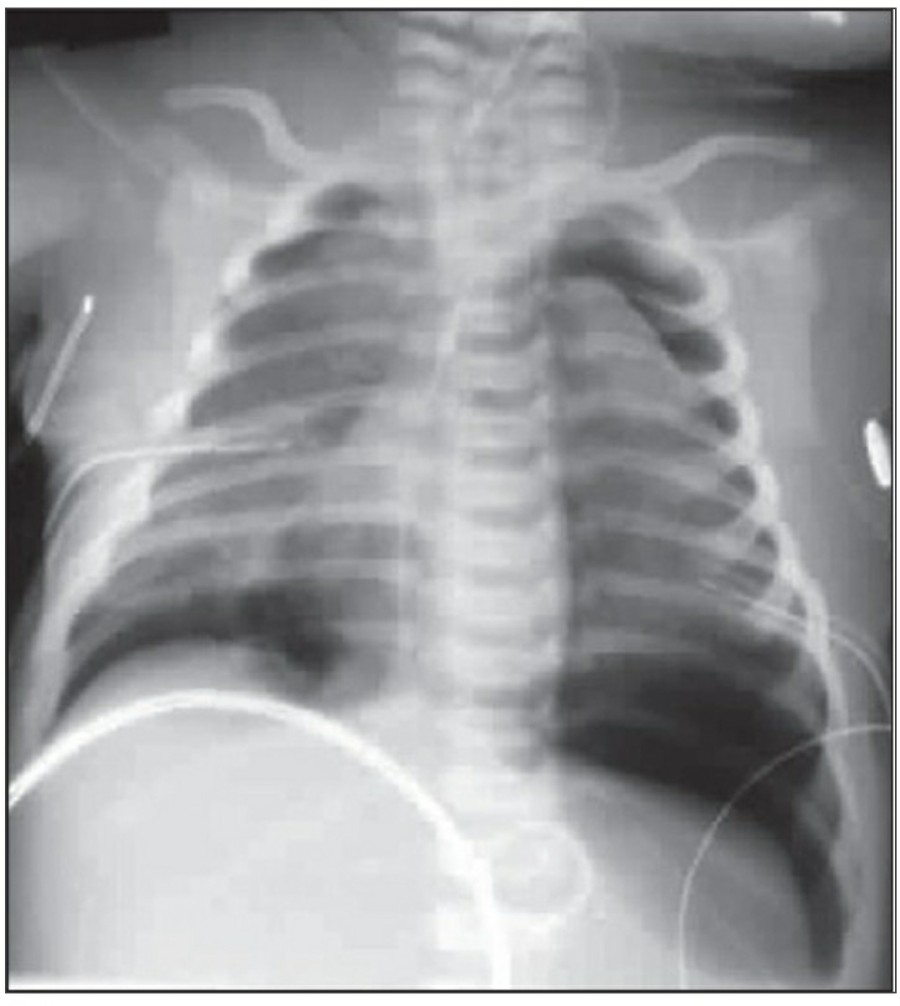

중환자에서 pneumothorax의 진단은 종종 supine radiograph에서 내릴 수 있다. Supine position에서 공기는 anteromedial 방향으로 모이게 되는데, apical air collection이 있을 경우 large pneumothorax가 있음을 시사한다. 공기는 lung과 diaphragm 사이의 subpulmonic location에 trap 되어 있을 수도 있다. 공기가 costophrenic sulcus로 anterolateral extension 될 경우, 이 costophrenic sulcus의 radiolucency를 증가시키는데, 이를 deep sulcus sign이라고 한다. Subpulmonic pneumothorax의 다른 특징으로 diaphragm의 superior surface와 IVC 윗부분이 뚜렷하게 보일 수 있다.

중환자에서 tension pneumothorax의 진단은 매우 힘들다. ARDS와 같은 lung의 병리적인 기전이 lung compliance를 감소시킴으로써 total lumg collapse를 막는다. 또한 tension pneumothorax의 특징인 mediastinal shift가 PEEP으로 인해 나타나지 않을 수 있다. Chest X ray 상에서 tension pneumothorax는 hemidiaphragm의 depression이나 heart border, SVC, IVC의 이동으로 나타날 수 있다.